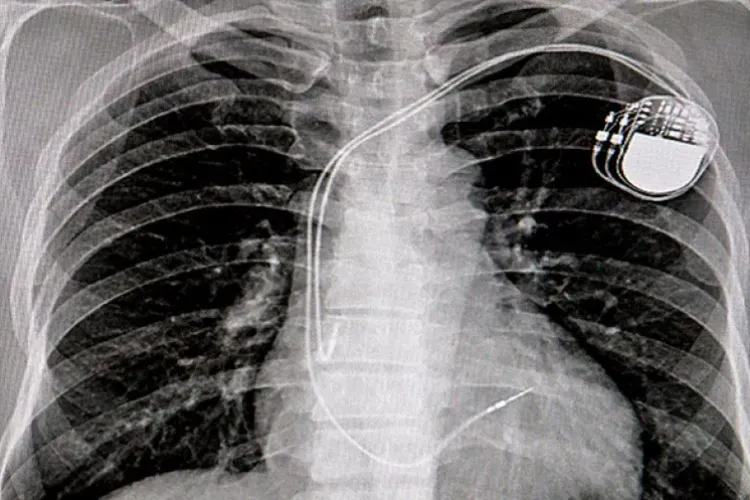

Doctorul Tesloianu a implantat dispozitive cardiace unor pacienți care nu aveau nevoie de o astfel de intervenție

„Consimțământul informat al pacientului" era falsificat. După semnarea de către pacienți, era adăugat, fără ca aceștia să știe, cu un pasaj scris de mână prin care și-ar fi dat acordul pentru pentru implantarea unor dispozitive refolosite.